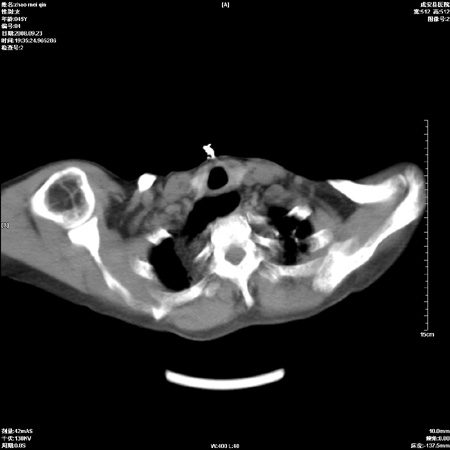

标题: CT15861:女 60 外伤后1小时 胸疼 [打印本页]

标题: CT15861:女 60 外伤后1小时 胸疼

外伤后1小时 胸疼 是外伤后引起的吗?

食道扩张明显下端逐渐变窄,倒像贲门失迟缓

未除外食道异物。如食道石长时间受阻。

考虑术后改变(胸腔胃),建议询问病史.

非外伤性改变,典型的贲门失迟缓症

食道扩张明显下端逐渐变窄,大量食物存留,象贲门失迟缓症。